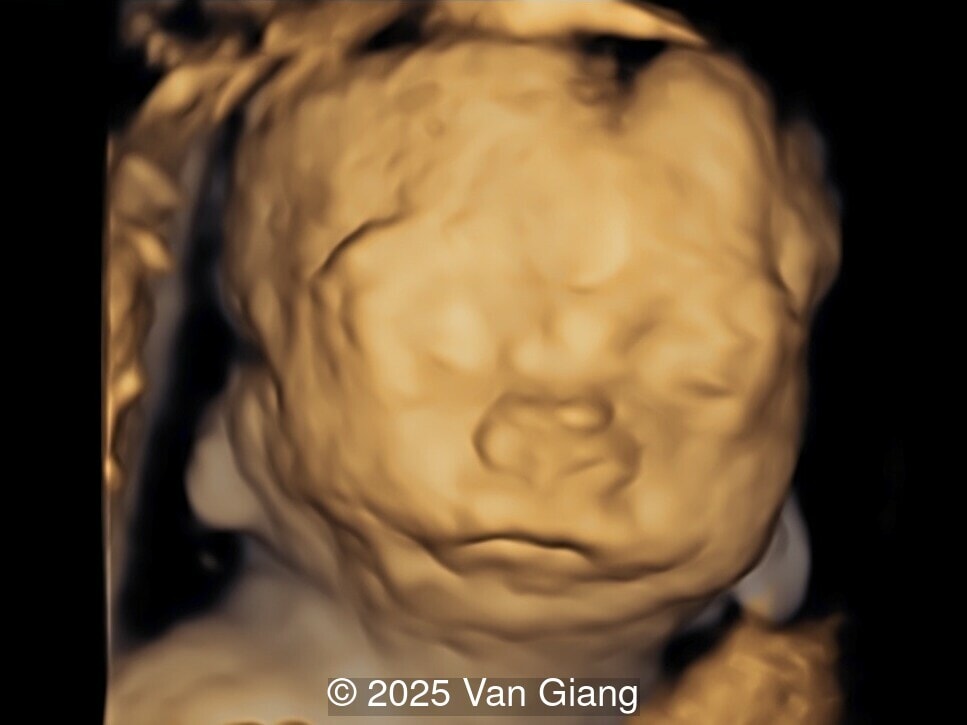

A 32-year-old primigravida presents at 20 weeks gestation without first trimester screening. Ultrasound reveals a small for gestational age fetus with the following anomalies:

Ultrasound revealed severe mandibular and zygomatic hypoplasia, glossoptosis, cleft palate, and micrognathia with an abnormal facial profile. Both upper limbs showed radial ray sequence with abnormal thumbs and shortened forearms. Unilateral clubfoot was also noted. No major cardiac or visceral anomalies were observed. Based on these findings, Nager syndrome was suspected.

fetal face

Image 2 fetal face